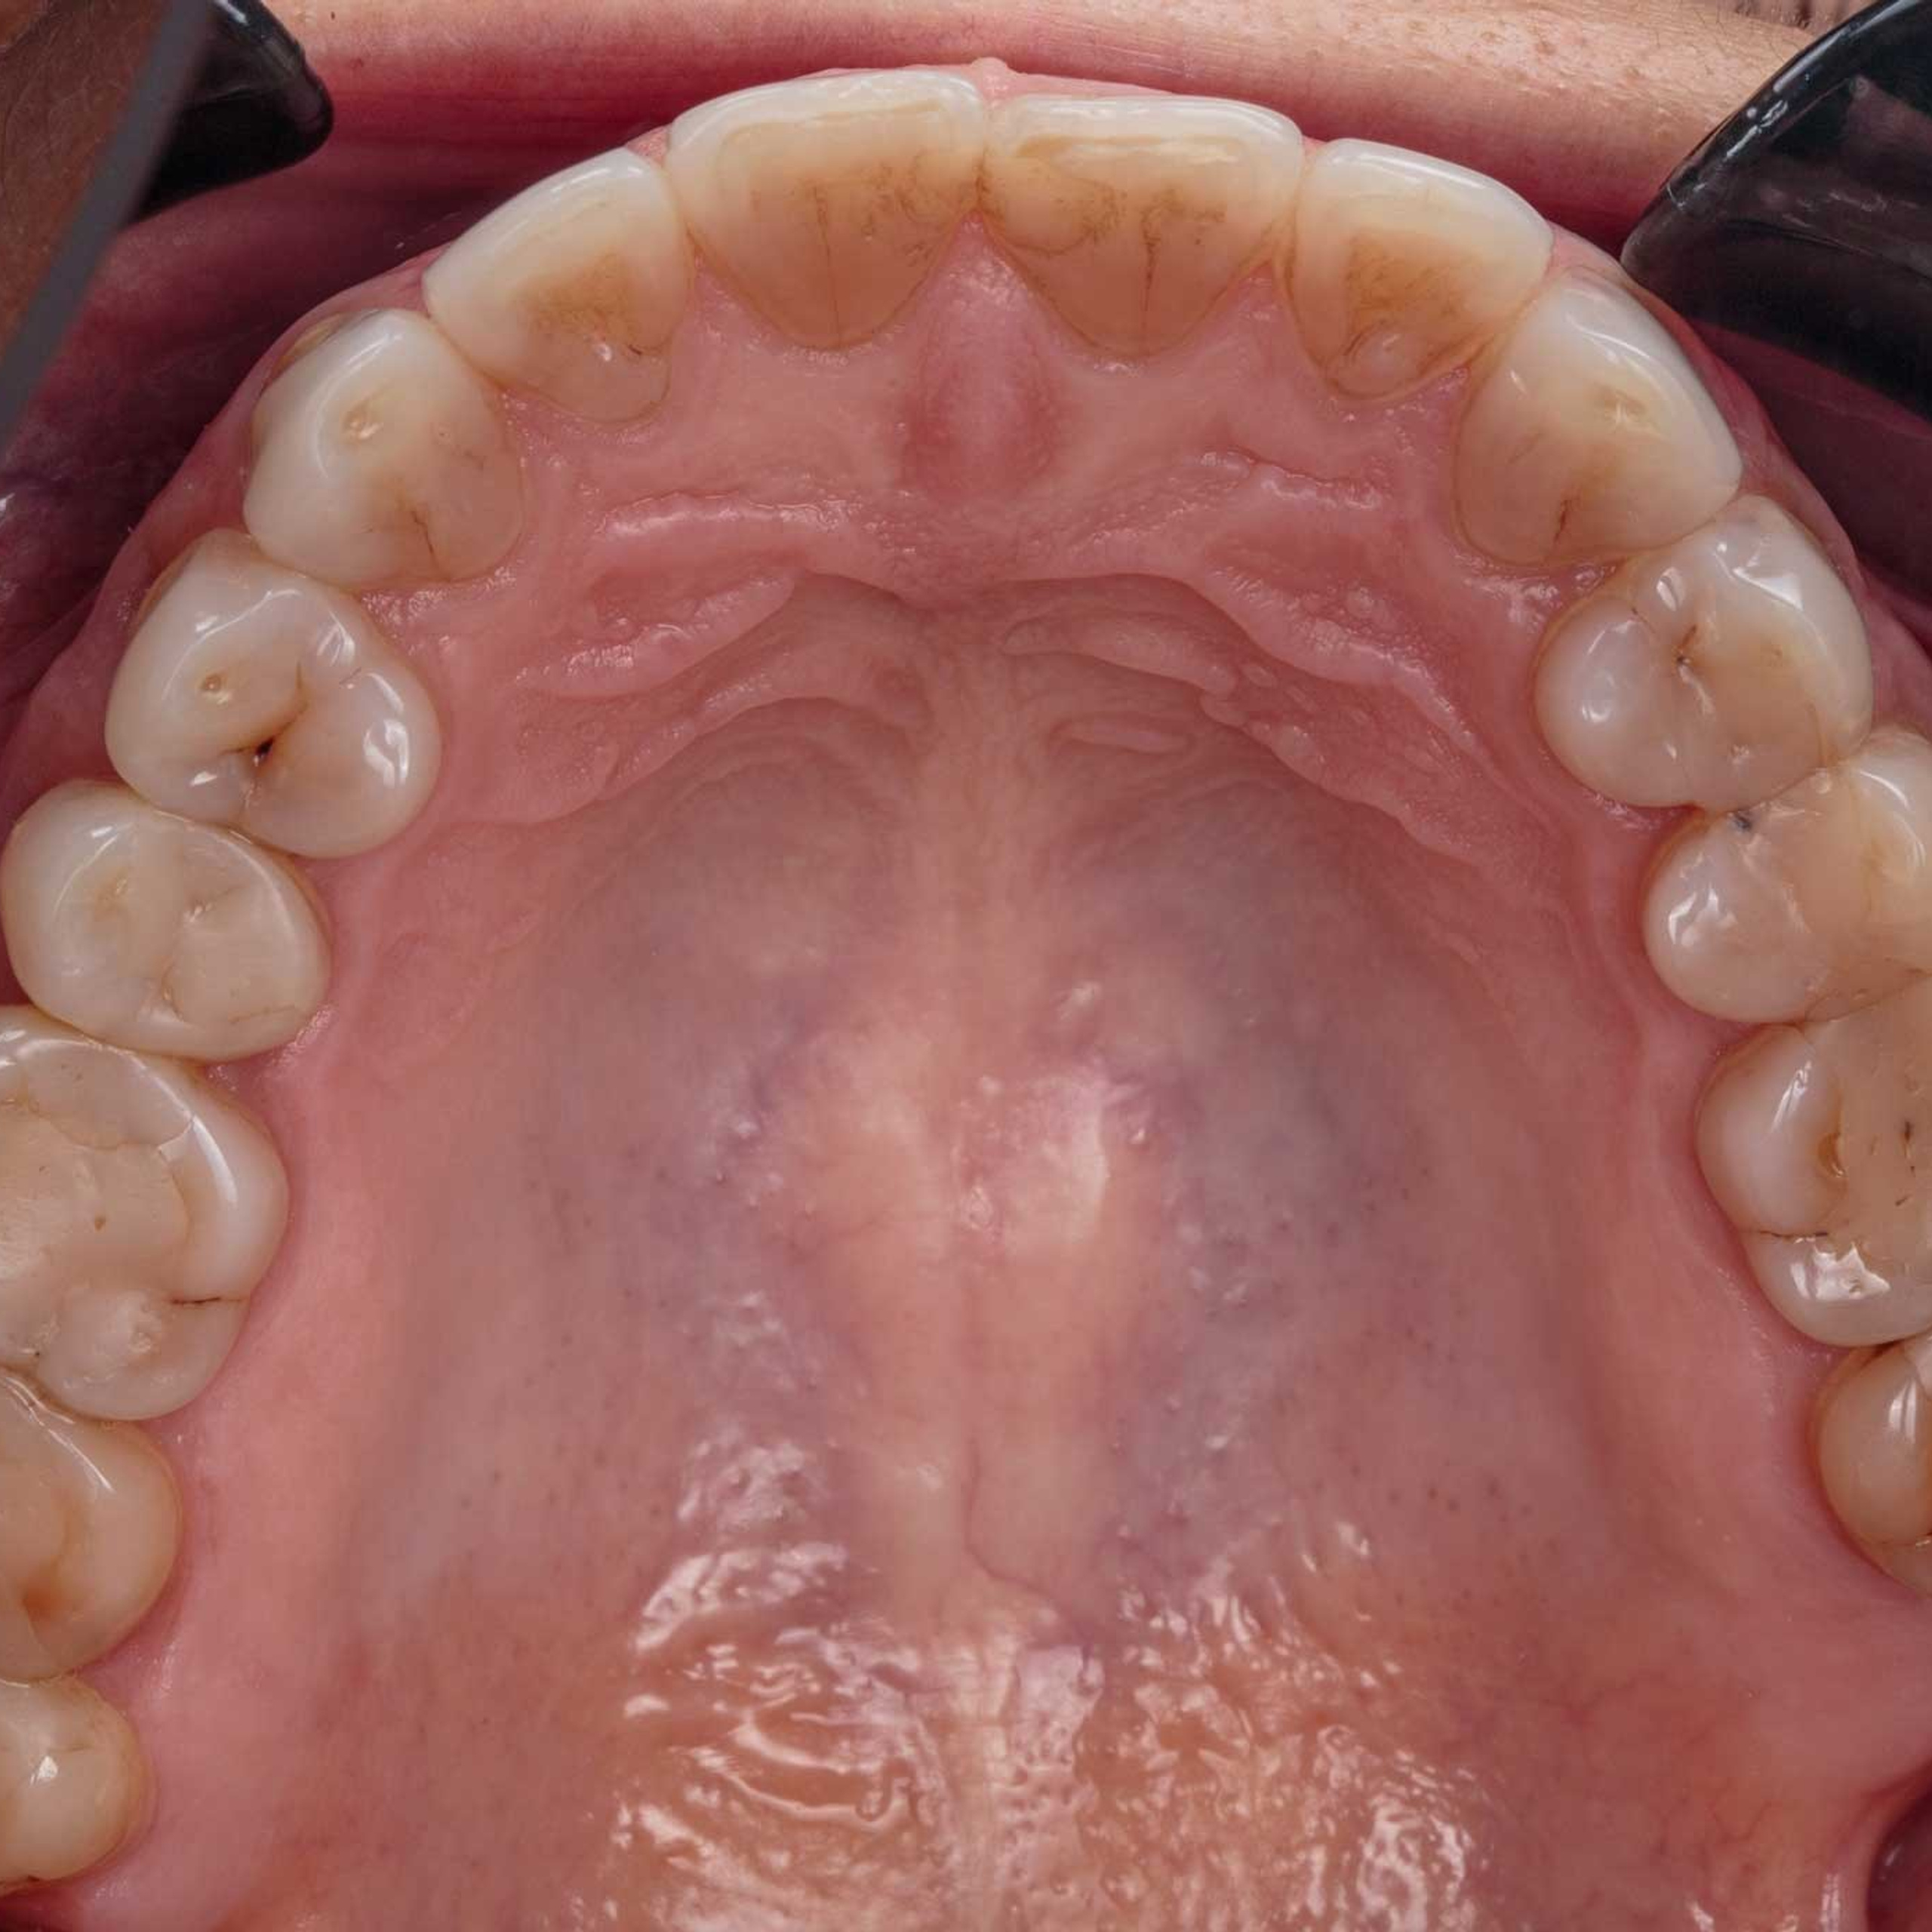

Фотографии учеников до обучения

Фотографии после обучения